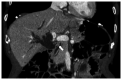

Metastatic choroidal carcinoma is rare and generally has a poor prognosis. The present case report describes a case of choroidal metastasis from distal cholangiocarcinoma, which was successfully managed using stereotactic radiotherapy (SRT). A 67-year-old Japanese man underwent pancreaticoduodenectomy for distal cholangiocarcinoma. The pathological stage was T2N0M0 stage IIA, according to the Union for International Cancer Control 8th edition. After surgery, the patient received adjuvant chemotherapy with oral TS-1® for 1 month. A total of 2 months after surgery, the patient was readmitted to hospital due to decreased visual acuity. Fundoscopy revealed a macular hole in the right eye that accounted for the decreased visual acuity. Additionally, Goldmann three-mirror contact lens examination revealed a 4-mm choroidal mass with a yellowish color situated at a considerable distance from the optic nerve. Magnetic resonance imaging revealed an enhanced choroidal mass. Based on the findings of ophthalmologic examinations and the patient's history of cholangiocarcinoma, they were diagnosed with choroidal metastasis from distal cholangiocarcinoma. SRT was administered at a total dose of 40 Gy divided into 8 Gy fractions. A total of 1 year after SRT, the patient achieved complete remission without decreased visual acuity. The patient remains alive and in good health without recurrence, 4 years after the diagnosis of choroidal metastasis. To the best of our knowledge, this is the second reported case of intraocular metastasis from cholangiocarcinoma. In conclusion, SRT may provide an opportunity to control metastatic choroidal carcinoma without decreasing visual acuity.